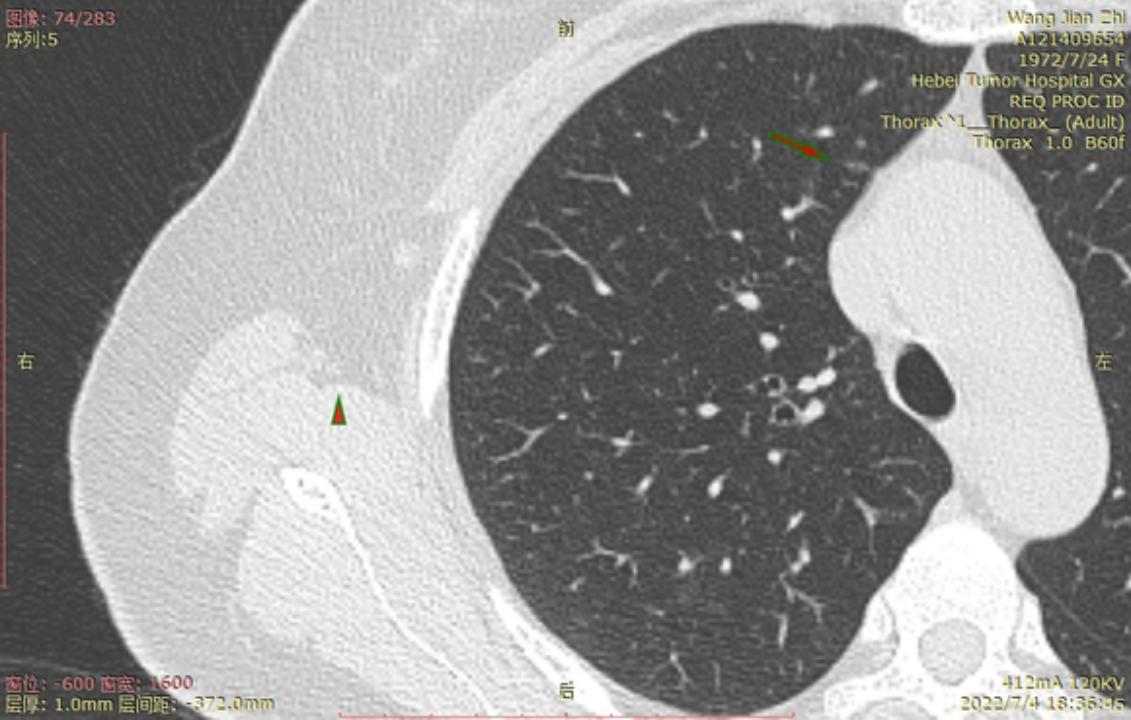

结2

结3